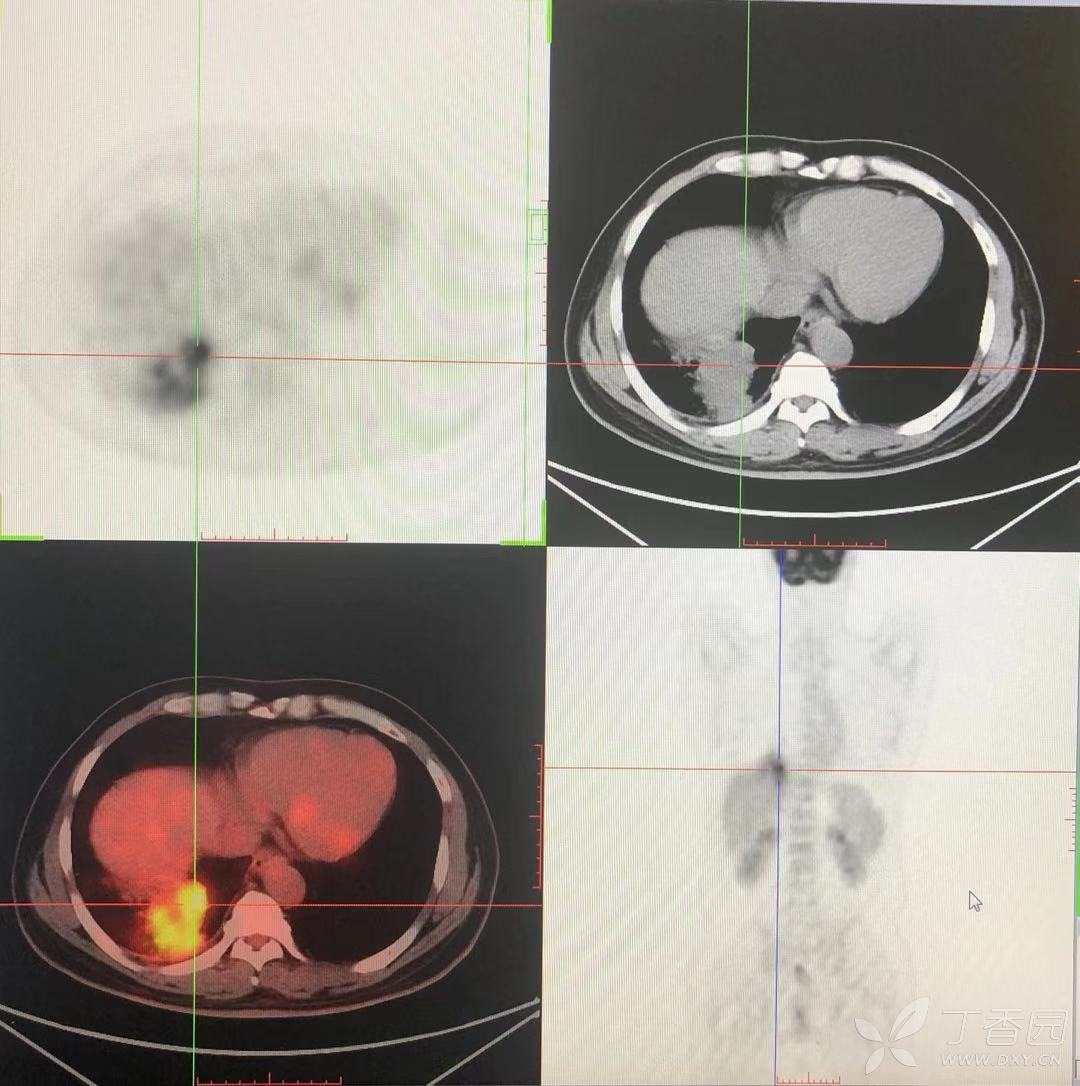

简要病史:咳嗽、咳痰,体重减轻5Kg+。

辅助检查:CT提示:右下肺占位伴周围炎症,CA待排,右侧少许胸腔积液。

临床诊断:右肺癌?待进一步检查。